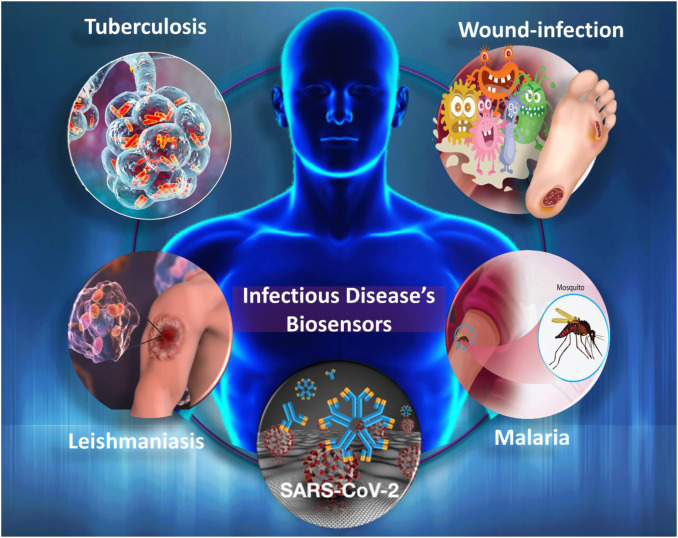

Genetic and Infectious Diseases

Cancer, Celiac Diseases, Blood Disorders, Tuberculosis

Natural remedies to stimulate DNA, repairing genes, treat mutations and ultimately restoring balance of life.